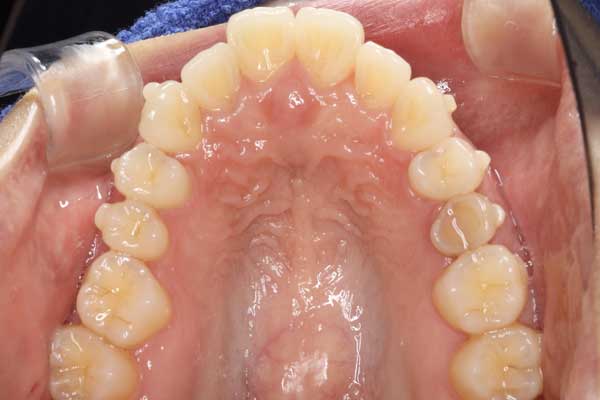

出っ歯を治したい

治療前

治療後

池畠 光朗

8ヶ月

440,000円(税込)